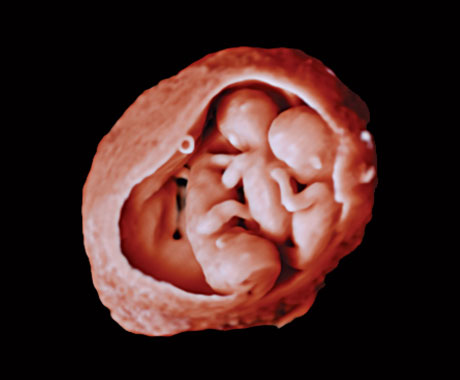

在该视频中,Michael Ruma 博士展示了飞利浦 V9-2 三维超声探头。V9-2 是飞利浦超声首个用于妇产科检查的纯净波三维机械探头,提供了卓越的图像质量和先进的人体工程学设计。V9-2 探头尤其适用于孕早期、孕中期和孕晚期产科检查的二维、三维、四维成像。

新型 V9-2 探头搭配 EPIQ Elite 卓越超声诊断系统,提供优质的妇产科成像:

先进的产科可视化工具实现逼真的胎儿渲染。